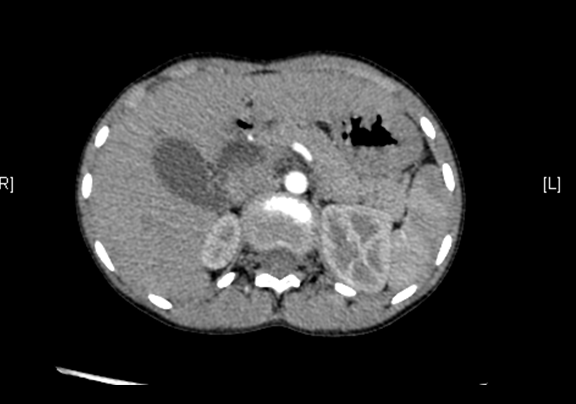

上腹部CT平扫:先天性胆管囊状扩张症并胆囊结石、胆囊炎症。

上腹部增强CT:肝总管-胆总管中上段梭形增宽,符合先天性胆管扩张所见(Ⅰ型)。

术前CT检查:

动脉期

静脉期